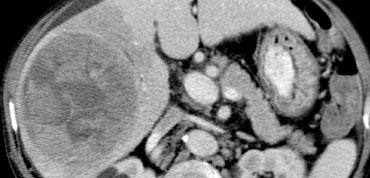

NECT, arterial and portal venous phase in a patient with Hepatitis C with two lesions in the liver (arrows).

Trong thì động mạch, chúng ta thấy hai tổn thương tăng sinh mạch.

Các hình ảnh phía trên cho thấy một tổn thương đồng tỷ trọng với gan trên CCLVT không tiêm thuốc.

Trong thì động mạch có sự ngấm thuốc, nhưng không đậm bằng tỷ trọng máu trong lòng mạch.

Trong thì tĩnh mạch cửa, tổn thương lại đồng tỷ trọng với nhu mô gan xung quanh và không thể nhìn thấy.

Nếu chỉ có thì tĩnh mạch cửa, chắc chắn bạn sẽ bỏ sót tổn thương này.

Các hình ảnh phía dưới cho thấy một tổn thương có thể nhìn thấy trên tất cả các hình ảnh.

Bạn thấy nó trên CCLVT không tiêm thuốc và có thể nhận xét rằng nó giảm tỷ trọng so với gan.

Tuy nhiên, nếu nhìn vào tỷ trọng máu trong lòng mạch, bạn sẽ nhận thấy rằng ở tất cả các thì, tổn thương có tỷ trọng tương đương với máu trong lòng mạch.

Vậy chúng ta có một ung thư biểu mô tế bào gan ở thùy phải trên các hình ảnh phía trên và một u máu ở thùy trái trên các hình ảnh phía dưới.

Điều quan trọng là phải xem xét tất cả các thì chụp.